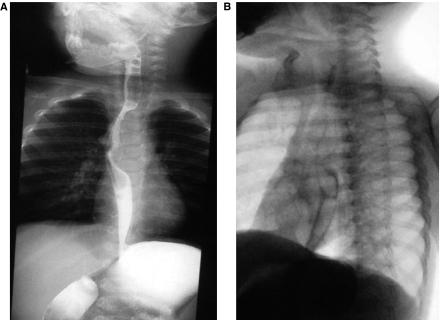

Duplications of esophagus are rare congenital anomalies and the second most common duplications of the gastrointestinal tract. This form of bronchopulmonary foregut malformation may appear as a cystic mediastinal mass. On chest radiographs they may be visible as middle or posterior masses. On CT they are well marginated and oppose the esophagus. Usually they are asymptomatic, unless they become infected or cause obstruction. We report a case of thoracic tubular duplication cyst in a 10-month-old boy who presented with persistent wheezing that was unsuccessfully treated in out-patient services.

食管重复畸形是一种罕见的先天性异常,是胃肠道第二大常见的重复畸形。这种形式的支气管肺前肠畸形可能表现为囊性纵隔肿块。在胸部 X 线片上,它们可能表现为中或后纵隔肿块。在 CT 上,它们边界清楚,与食管相对。通常情况下,它们无症状,除非感染或引起梗阻。我们报告了 1 例 10 个月大男孩的胸管状重复囊肿病例,该男孩表现为持续性喘息,在外院治疗无效。